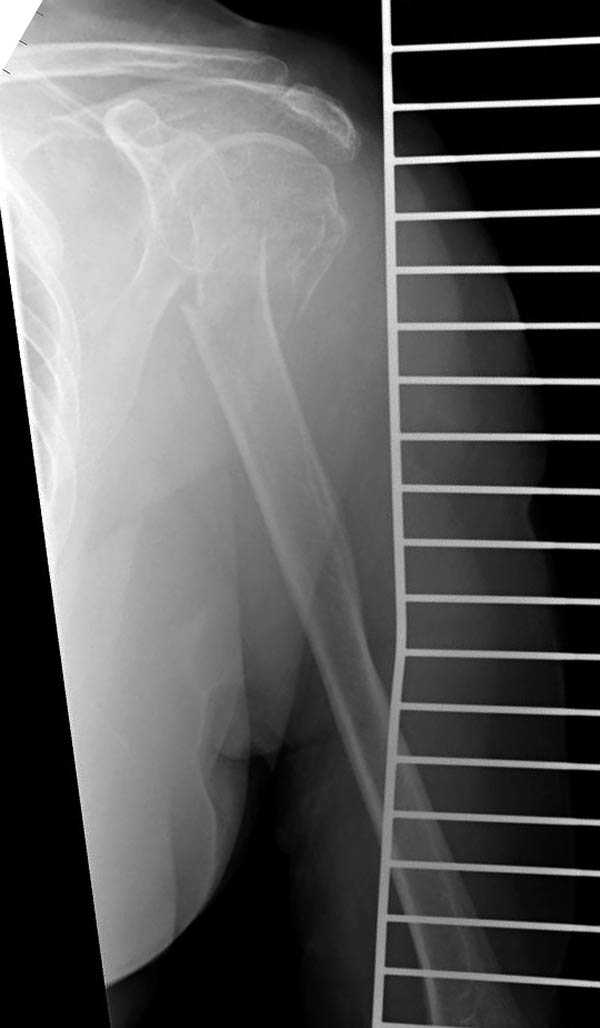

Судя по снимкам головка ротирована,успех закрытой репозиции, на мой взгляд, сомнителен, надо оперировать.

Судя по Р-граммам имеется оскольчатый перелом головки плеча. Во время открытой репозиции имеется большой риск "развалить" перелом, что значительно ухудшит кровоснабжения отломков. А так, на мой взгляд контакт м\у отломками достаточный, не смотря на наличие ротационного смещения головки думаю лучше продолжать консерватикное лечение. С уважением.

Судя по снимкам еще имеется перелом головки плеча, и чрезкостный отрыв вращательной манжеты. Для уточнения характера перелома не иешало бы сделать КТ. Если вести консервативно, то после сращения перелома будет ограничение движений в суставе не устраивающее больную. Я склоняюсь к оперативному лечению( накостный остеосинтез Т- Г образная пластина, лучше LCP для проксимальног плеча, обязательно подшить на место манжету).

В соответствии с работами Neer данный перелом можно классифицировать как однофрагментарный, так как нет диастаза более 1 см и углового смещения более 45 градусов - такие переломы лечатся консервативно. Рентген контроль каждые 10 дней- если смещение не увеличивается, то через 3-4 недели разработка движений в суставе

Уважаемый Сергей! Вы правильно написали критерии, но недооценили степень смещения в переломе хирургической шейки. Посмотрите ещё раз, это Two part fracture.